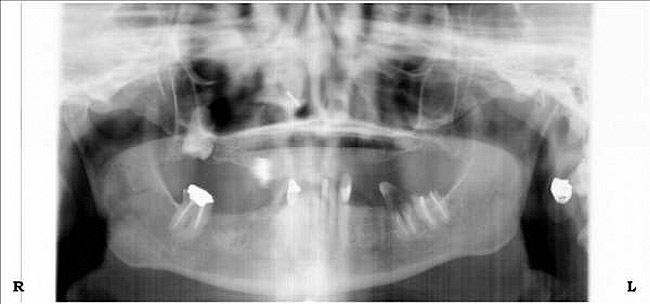

Figure 10a  Supra-eruption of the opposing arch, thus diminishing crown height space.

Figure 10a

Figure 10b  Supra-eruption of the opposing arch, thus diminishing crown height space.

Figure 10b

Figure 10c  Traditional fixed prosthodontics performed to level the opposing arch and regain sufficient crown height space.

Figure 10c

Figure 10d  Traditional fixed prosthodontics performed to level the opposing arch and regain sufficient crown height space.

Figure 10d